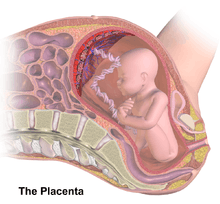

Placental circulation

Maternal placental circulation

In preparation for implantation of the blastocyst, the uterine endometrium undergoes "decidualisation". Spiral arteries in decidua are remodeled so that they become less convoluted and their diameter is increased. The increased diameter and straighter flow path both act to increase maternal blood flow to the placenta. The relatively high pressure as the maternal blood fills intervillous space through these spiral arteries bathes the fetal villi in blood, allowing an exchange of gases to take place. In humans and other hemochorial placentals, the maternal blood comes into direct contact with the fetal chorion, though no fluid is exchanged. As the pressure decreases between pulses, the deoxygenated blood flows back through the endometrial veins.

Maternal blood flow is approximately 600–700 ml/min at term.

Fetoplacental circulation

Deoxygenated fetal blood passes through umbilical arteries to the placenta. At the junction of umbilical cord and placenta, the umbilical arteries branch radially to form chorionic arteries. Chorionic arteries, in turn, branch into cotyledon arteries. In the villi, these vessels eventually branch to form an extensive arterio-capillary-venous system, bringing the fetal blood extremely close to the maternal blood; but no intermingling of fetal and maternal blood occurs ("placental barrier").[9]

Endothelin and prostanoids cause vasoconstriction in placental arteries, while nitric oxide causes vasodilation.[10] On the other hand, there is no neural vascular regulation, and catecholamines have only little effect.[10]

The fetoplacental circulation is vulnerable to persistent hypoxia or intermittent hypoxia and reoxygenation, which can lead to generation of excessive free radicals. This may contribute to pre-eclampsia and other pregnancy complications.[11] It is proposed that melatonin plays a role as an antioxidant in the placenta.[11]